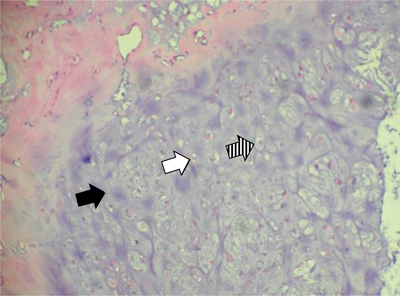

Figure 9

Case 2 – Histopathology of the resected specimen. Hematoxylin eosin staining, 200×: cartilaginous tissue with moderate cellularity. Note chondroid matrix (black arrow) with interspersed small (white arrow) to medium sized (dashed arrow) chondrocytes with no atypia or mitotic activity. There is absence of necrosis.

Histopathologically, JCC is characterized by a cellular hyaline to myxoid cartilage lacking nuclear hyperplasia. Nuclei are small and round with condensed chromatin. Slightly larger nuclei with open chromatin and small nucleoli are common. The cells can be evenly distributed or arranged in small clusters. More than one cell per lacuna as well as binucleated cells can be present but those features are rather occasional. Mitotic activity is absent [1]. Focal calcifications and mucoid matrix degeneration can be observed [2].